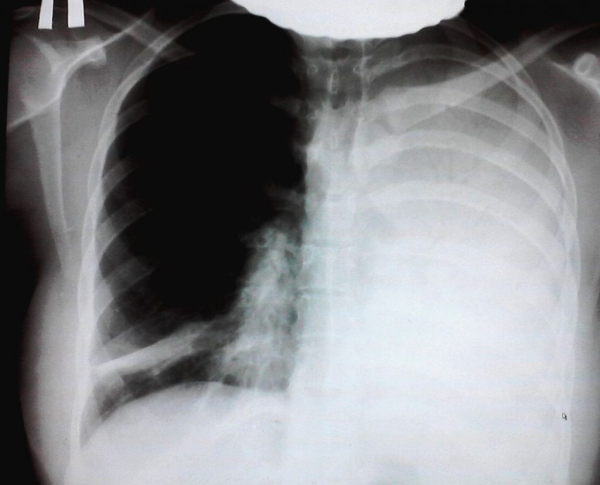

Наличие гемангиома в грудной клетке может затруднять дыхание и провоцировать иные проблемы в работе соседних органов и систем.

Гемангиомы грудной клетки классифицируют по структуре, локализации, размерам.

Если гемангиома располагается на коже груди, то ее замечают, когда проводят внешний осмотр пациента. У детей она появляется через несколько дней после рождения. Врач предварительно ставит диагноз и для подтверждения проводится дополнительное обследование, которое включает: